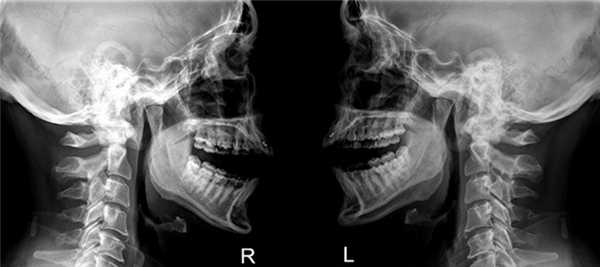

Рентгенография височно-нижнечелюстного сустава

Рентген височно-нижнечелюстного сустава представляет собой один из наиболее распространенных методов диагностики, который позволяет выявить переломы и смещения костей, воспалительные и патологические процессы. Это исследование предельно точно показывает взаиморасположение костных тканей и само строение ВНЧС.

Эта методика используется несколько десятков лет, но ее актуальность сохраняется и по сей день. Основным преимуществом рентгенограммы является передача четкого изображения состояния твердых структур исследуемой области. Работа аппарата основывается на фиксации уровня ослабления радиоактивных лучей, проходящих через твердые и мягкие ткани.

Что показывает снимок ВНЧС?

Снимок ВНЧС - это черно-белое графическое изображение, которое позволяет определить ширину суставной щели, соотношение всей костей, образующих сустав, а также определить имеющиеся патологические процессы.

Для взрослых пациентов лучше всего проводить обзорный метод рентгенографии при помощи дентального аппарата. Чтобы получить наиболее достоверную информацию, исследование проводится с закрытой и открытой челюстью.

Снимок височно-нижнечелюстного сустава показывает следующие результаты:

- В стоматологии оценивается причина неправильного прикуса, выявляются зубно-челюстные аномалии, а также исследуется общее состояние перед предстоящим зубным протезированием.

- Диагностика отита, гнойного паротита и остеомиелита.

- Выявление вывихов, подвывихов и переломов.